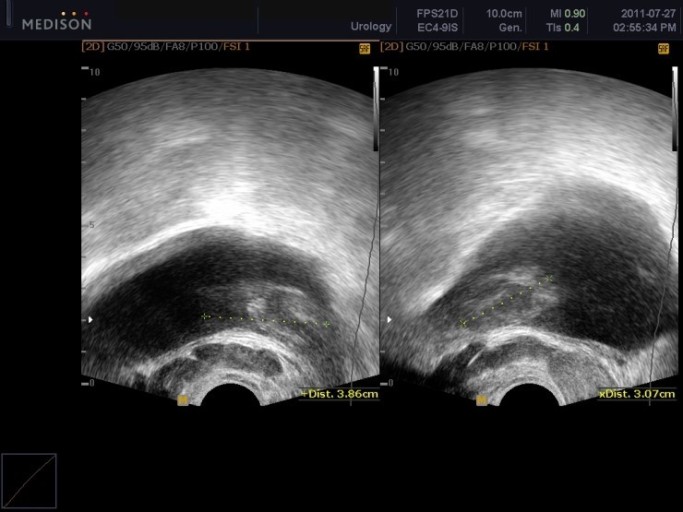

- 전립선암 선별검사(PSA 검사) 필수

- 대상: 특별한 증상이 없더라도 50세 이상 남성은 매년 1회 혈액 PSA(전립선 특이항원) 검사와 직장 수지 검사를 받는 것이 권장됩니다.